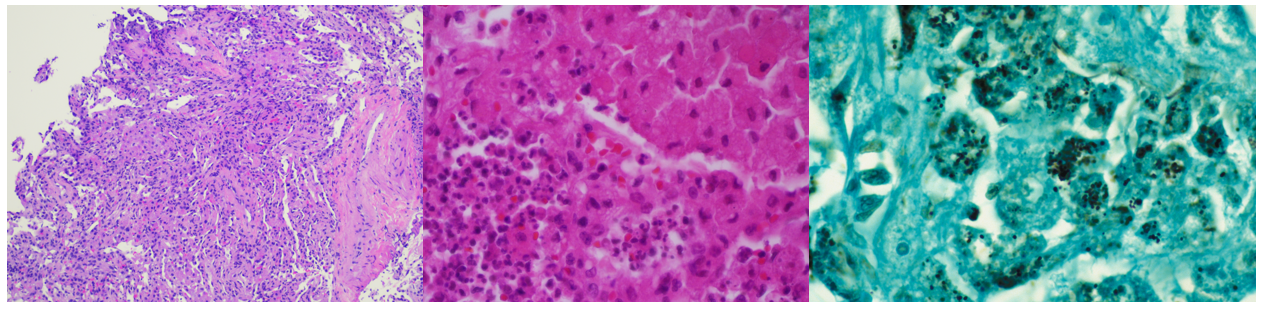

Gram stains of both the tissue and BAL fluid were generally unremarkable. Histopathological analysis of the transbronchial tissue revealed changes suggestive of organizing pneumonia with mononuclear infiltrate (Image 2, left). Bacterial growth of a predominant organism from both the BAL and biopsy tissue was observed on plates after 48 hours on blood and chocolate agars but was absent on MacConkey agar. At 96 hours, the colonies of the organism had become mucoid, slightly pink and had coalesced (Image 1, right). Gram staining of the growth revealed short, poorly staining gram positive coccobacilli with a beaded appearance. Due to the incomplete gram staining of this isolate, modified acid-fast staining was attempted which was positive (Image 1, left). The organism was both catalase- and urease-positive. The isolate was subsequently identified by MALDI-TOF MS as Rhodococcus equi, and the patient was discharged from the hospital on imipenem and linezolid.

R. equi is a member of the aerobic actinomycetes. Like Nocardia sp., the cell wall of R. equi contains mycolic acids which lead to positivity when stained with a modified acid-fast stain. The organism is a facultative, intracellular pathogen surviving within macrophages and histiocytes, leading to granulomatous inflammation, eventually leading to necrosis.2 Immunosuppression (including HIV infection or immunosuppressive therapy) is a major risk factor for R. equi infection, as most clinical cases are reported in this setting. In immunocompromised hosts, the spectrum of disease manifestations of R. equi are diverse, but most commonly (approx. 80%) include pulmonary involvement3 with upper lobe cavitary pneumonia.4 Characteristic malakoplakia (an infiltration of foamy histocytes with intracellular bacteria and basophilic inclusions name Michaelis-Gutmann bodies)1 can be associated with R. equi infection. These structures were noticeably absent in this patient’s case despite the observed histocyte aggregation and mononuclear infiltrate (Image 2, center, left).